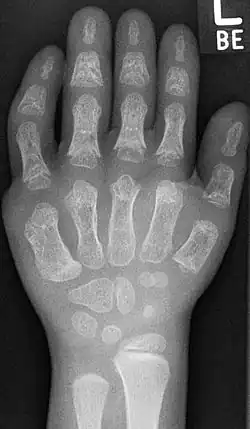

Die äußerlichen Hauptsymptome sind der Kleinwuchs, Thoraxdeformität mit verkürzten Rippen, die Polydaktylie, sowie hypo- oder dysplastische Fingernägel und Zähne. Die Polydaktylie ist an den Händen üblicherweise beidseitig, postaxial (Außen) auf der ulnaren Seite. Bei etwa 10 % der Patienten sind auch die Füße von der Polydaktylie betroffen. Häufig ist zwischen der Großzehe (Hallux) und der zweiten Zehe ein größerer Zwischenraum.[2] Die Extremitäten wirken meist plump. Die mesomele (mittlere Anteile, das heißt Unterarm beziehungsweise -schenkel) und akromele (distale Anteile, das heißt Finger beziehungsweise Zehen) Verkürzung der Gliedmaßen ist sehr häufig. Sehr oft können die Patienten die Hand nicht zu einer Faust ballen.[3][4]

Radiologische Kriterien sind:[14]

- Beckendysplasie mit Spornbildung medial am Pfannendach

- Vorzeitige Ossifikation der proximalen Oberarm- und Oberschenkelepiphyse

- Überproportional kurze Unterarme und Unterschenkel

- Verbreiterung der Tibia proximal, nach medial verlagertes Ossifikationszentrum mit massivem Genu valgum

- zu kurze Fibula

- Verkürzte Fingerglieder mit Zapfenepiphysen der Mittel- und Endphalangen

Häufig Hexadaktylie, Fusion von Handwurzelknochen (Os hamatum und Os capitatum) Häufig Radiusköpfchenluxation und Patellaluxation, postaxiale Polydaktylie[15].